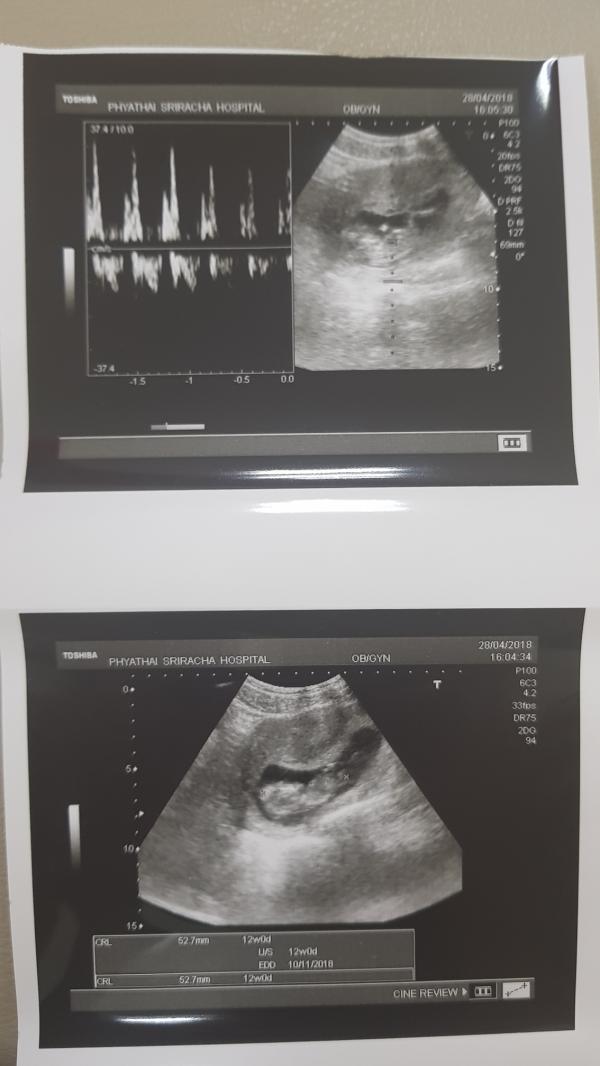

12я неделя❤❤❤ Первый раз распечатали УЗИ и услышали сердечко ❤❤❤ Сегодня решили сменить своего врача частной практики на врача в платном госпитале Phyathai в городе Сирача. Очень крутой уровень! Сдали анализы на кровь на антитела, оказалось, что у предыдущего врача результат был неверный! Мы думали, что у нас есть эти анти тела в малой дозе! Но .. Нет) мы рады , но все равно сказали сдавать этот анализ каждый месяц!